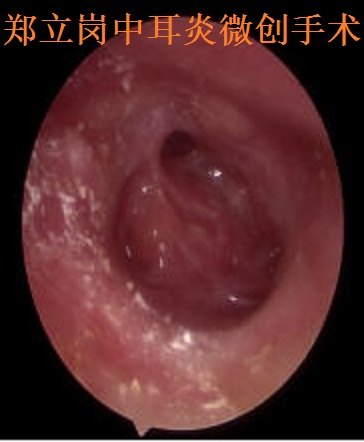

慢性中耳乳突炎感染期耳内镜微创手术第343广

428x408 - 26KB - JPEG